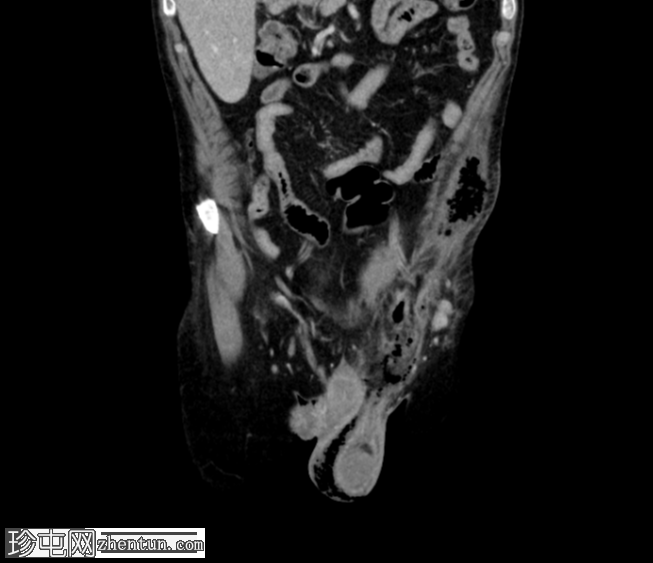

矢状C+门静脉期

疑似乙状结肠憩室炎。左侧直疝,乙状结肠壁一段内有气泡——最有可能是嵌顿疝,憩室穿孔是福尼尔坏疽的病因。

福尼尔坏疽由此沿精索向左半阴囊延伸,并沿腹外斜肌筋膜向头部延伸。